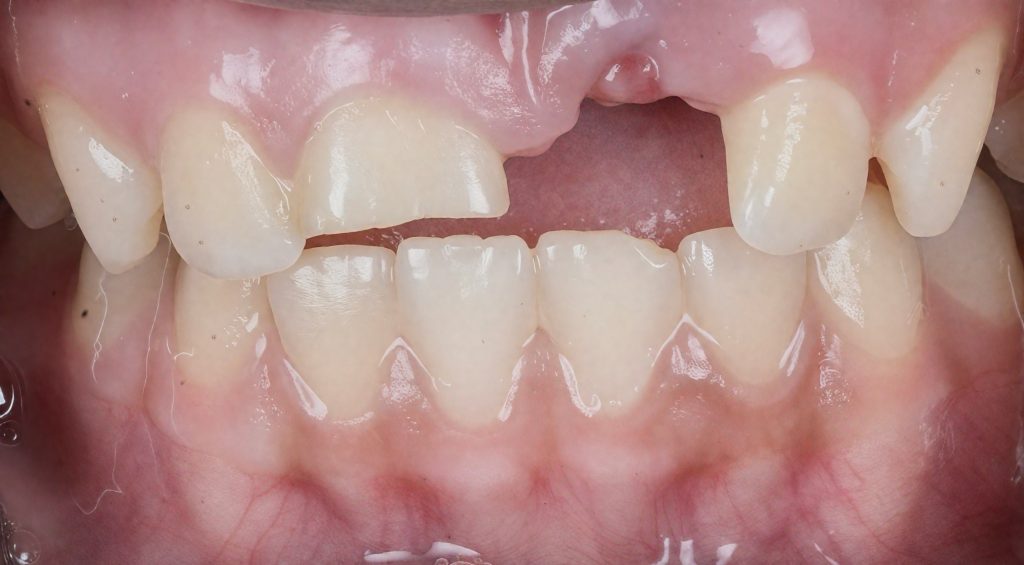

Chief Complaint

“I injured my front tooth a long time ago and it has now discoloured and become painful.”

History

•History of trauma to anterior maxillary region.

•Tooth remained untreated initially.

•Later developed pulpal necrosis and arrested root development.

•Patient sought treatment due to aesthetic concern and occasional discomfort.

Clinical Findings

•Tooth: Maxillary Central Incisor (#11)

•Immature root with open apex

•Discolouration present

•No mobility or sinus tract

•No periodontal pocketing

•Electric pulp test negative